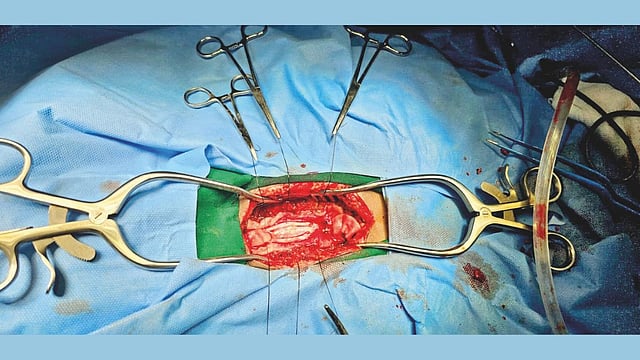

बेळगाव : बिम्समध्ये मुलीच्या पाठीतून काढण्यात आलेल्या ट्युमरची गाठ (Pudhari File Photo)

बैलहोंगल तालुक्यातील तिगडी गावातील बसवराज माविनकट्टी यांची सोळा वर्षीय मुलगी लक्ष्मीच्या पाठीच्या कण्यातील ट्युमरच्या उपचारासाठी 13 सप्टेंबर रोजी बिम्स रुग्णालयात दाखल करण्यात आले होते. तिची प्रकृती झपाट्याने बिघडत होती. काही दिवस निरीक्षण केल्यानंतर बिम्सचेे न्यूरोसर्जन डॉ. बसवराज बिरादार-पाटील यांनी 15 सप्टेंबर रोजी शस्त्रक्रिया करण्याचे नियोजन केले. त्यानुसार बिरादार पाटील आणि डॉ. संजीव राठोड यांनी नर्सिंग स्टाफ आणि भूल देणार्‍या कर्मचार्‍यांसह लक्ष्मीच्या पाठीच्या कण्यातील गाठ शस्त्रक्रियेद्वारे यशस्वीरित्या काढून टाकली आणि तिला बरे केले.